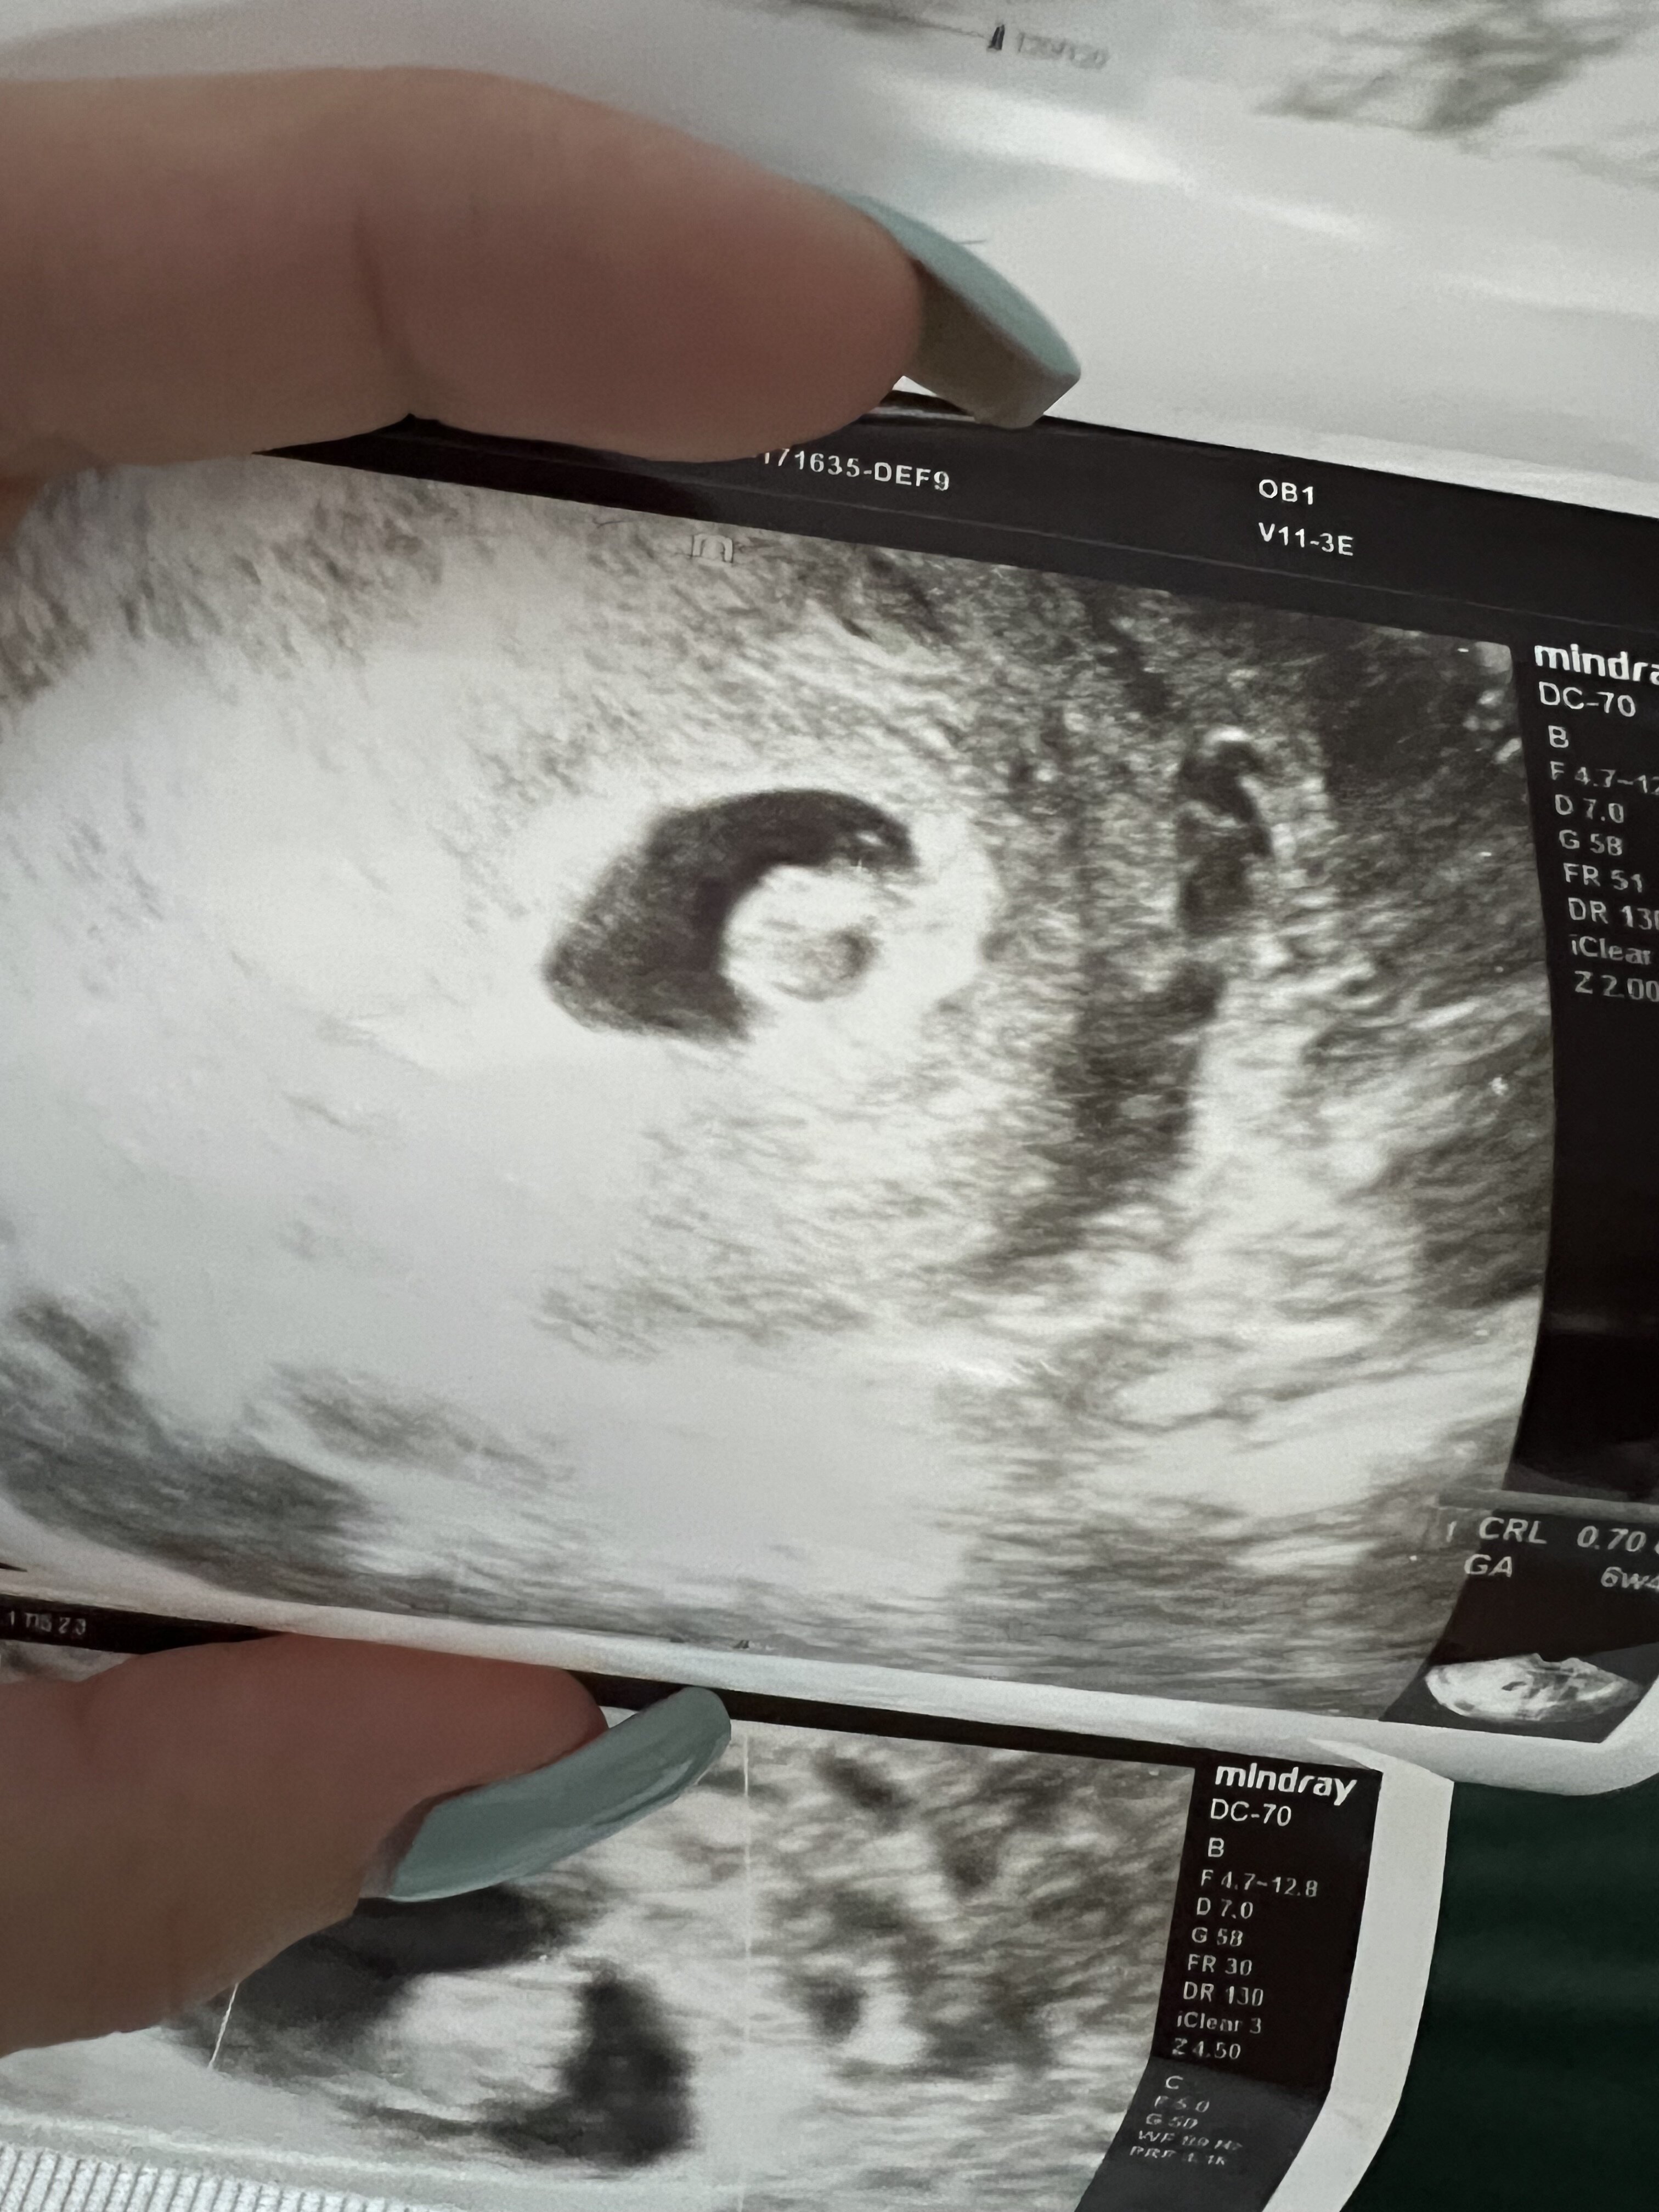

Właśnie wracam od ginekologa i niestety po pierwszej wizycie z płaczem.

Według obliczeń 6tc z czego pęcherzyk płodowy mniejszy od płodu o około tydzień…I najgorsze ze brak echo serduszka ,myślicie ze serce jeszcze może się pojawić? Ginekolog powiedział ze nie widzi takiej szansy